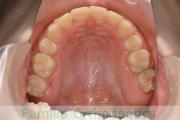

上の前歯の並びが気になるのできれいにしたい、ということで来院されました。マウスピース型矯正装置のひとつ、インビザライン/InvisalignR(薬機法および医薬品副作用被害救済制度の対象外)を用いて治療しました。

非抜歯で2年弱、20回程度の通院で治療が完了しました。

マウスピース矯正は、患者さんの協力に治療結果が左右されるところはリスクと言えるかもしれません。